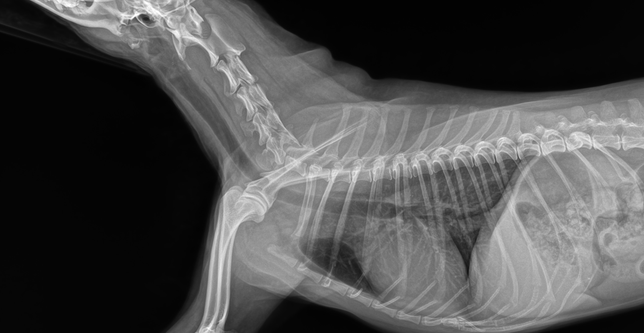

- 반려동물 건강반려동물Q. 기관지협착인가요 기관협착인가요? 아니면 둘다 있나요? 기관지염이 있나요? 기관염이 있나요?질문1. 기관지협착인가요 기관협착인가요? 아니면 둘다 있나요?질문2. 기관지염이 있나요? 기관염이 있나요?질문3. 사진 좌측상단에 날짜부분에 굉장히 좁아보이는데 이부분이 후두인가요? 후두가 부어있는건가요?질문4. 약간의 기도협착이 있나요?질문5. 협착과 염 상태가 어느정도인지 상중하로 알려주시면 감사하겠습니다